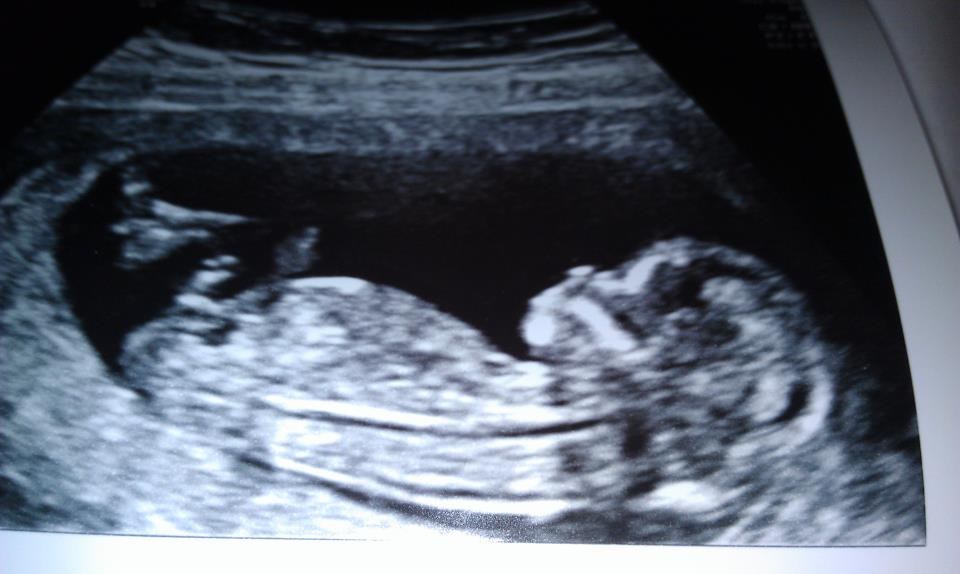

så har vi været til nf og alt var som det skulle være og vi er så glade og ville lige dele et lille billede a guldklumpen

har fået ny termin 19/07-2012

Næhhh, et super godt billede af din bebs :-) godt at høre, at NF gik godt. Skal selv ud på OUG i dag og have lavet en NF...er meget spændt og håber at alt som det skal være :-)